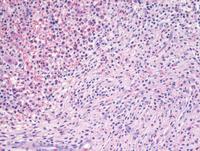

A 70-year-old man presented with persistent eosinophilia. Hb 133 g/L, WBC 70 x10^9/L, Neutrophils 57 x10^9/L, Eosinophils 15.7 x10^9/L, platelet 186 x10^9/L. Bone marrow aspirate is hypercellular. Granulopoiesis is hyperplastic with no excess of blasts.  Eosinophils and precursors are markedly increase accounting for 65% of total nucleated cells.  Some have abnormal lobulation, cytoplasmic vacuolation and patchy granulation. BCR-ABL and JAK2 were negative by PCR. Leukaemia fusion gene (Q30) screen was positive for the FIP1L1-PDGFRA translocation. FISH indicates loss of CHIC2 at 4q12. Other hematologic neoplasms or reactive eosinophilia were excluded.